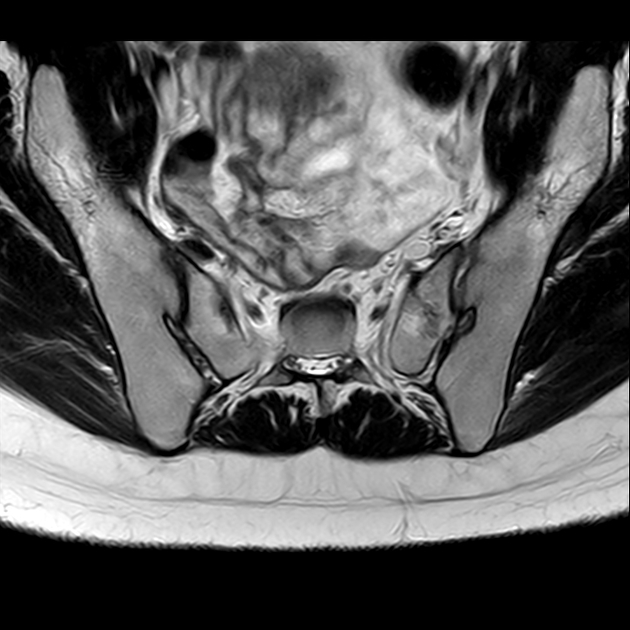

磁共振检查:

T1

磁共振影像表现